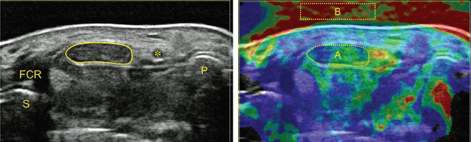

The simultaneous application of structural and functional imaging techniques is described as multiparametric (MP) (Fig. 9). Studies have shown that the MP approach results in greater diagnostic accuracy (Fig. 10).

- Sonography of carpal tunnel: definition of cut-off values

- Sonographically guided (SG) injections in CTS: sonoelastographic appearance

Fig. 15: Carpal tunnel syndrome: diagnosis by means of median nerve elasticity—improved diagnostic accuracy of US with sonoelastography (Miyamoto et al., 2014).